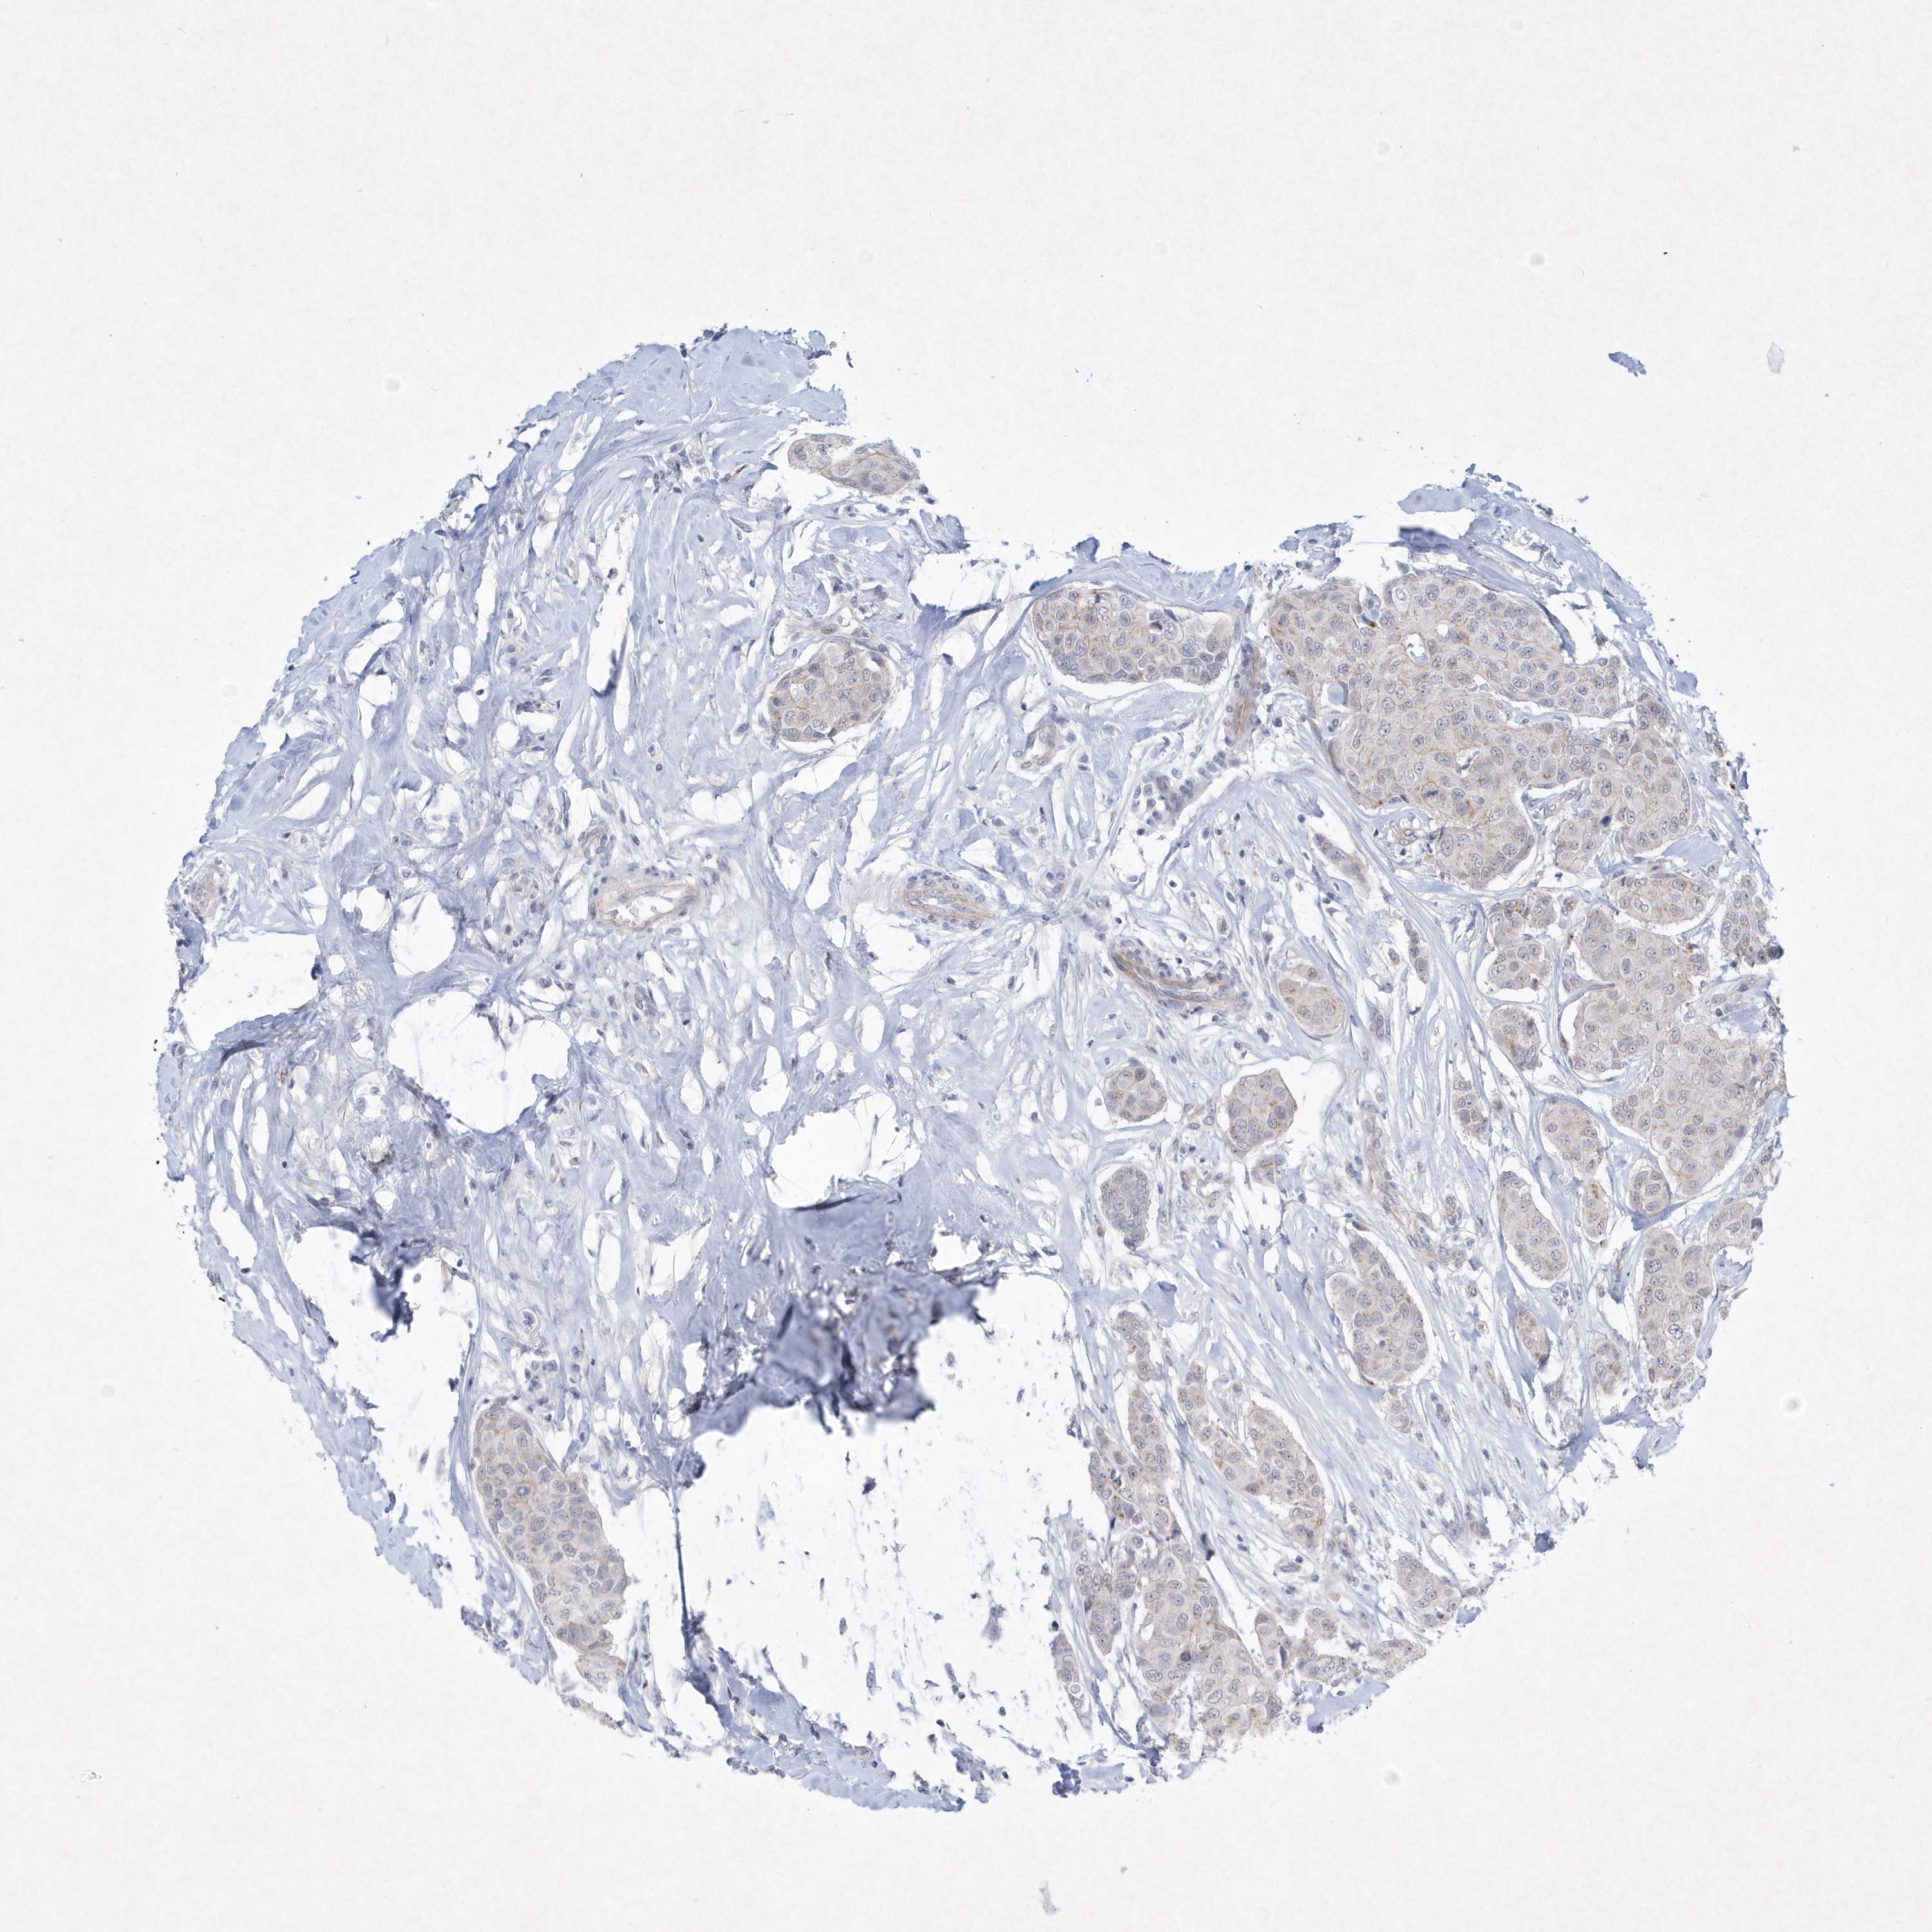

BRCA TCGA BRCA VALIDATION PROTEIN EXPRESSION